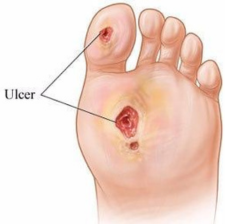

diabetic foot ulcer

A diabetic foot ulcer is an open sore or wound that occurs in approximately 15 percent of patients with diabetes, and is commonly located on the bottom of the foot. Of those who develop a foot ulcer, six percent will be hospitalized due to infection or other ulcer-related complication.

Debridement Of Non-healing Ulcers

Diabetic Foot Management

Skin Grafting